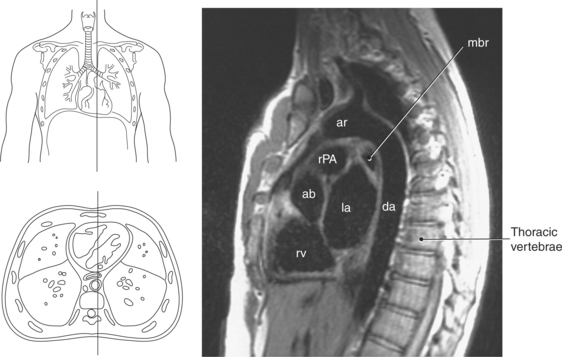

Figure 6.60 Sagittal, T1-weighted MR scan with aortic arch and descending aorta.

Key: ar, aortic arch; da, descending aorta; mbr, mainstem bronchi; rPA, right pulmonary artery; ab, aortic bulb; la, left atrium; rv, right ventricle.

Blood travels to and from the heart through the great vessels, which include the aorta, pulmonary arteries and veins, and superior and inferior venae cavae (Figures 6.54 and 6.55). The aorta is the largest artery of the body and can be divided into the ascending aorta, aortic arch, and descending aorta. The ascending aorta begins at the base of the left ventricle at the level of the sternal angle, then curves superiorly and posteriorly as the aortic arch over the root of the left lung. The top of the aortic arch is approximately at T3 (Figures 6.56 and 6.57). The arch continues as the descending aorta posterior to the left bronchus and pulmonary trunk, on the left side of the vertebral body of T4 (Figures 6.58 and 6.59). The descending aorta passes slightly anterior and to the left of the vertebral column as it descends through the thoracic and abdominal cavities (Figure 6.60). While in the thoracic cavity, the descending aorta is commonly called the thoracic aorta, and while in the abdominal cavity, it is called the abdominal aorta. The pulmonary trunk is the origin of the right and left pulmonary arteries and lies entirely within the pericardial sac. It arises from the right ventricle and ascends in front of the ascending aorta, courses posteriorly and to the left, where it bifurcates at the level of the sternal angle (T4) into the right and left pulmonary arteries (Figures 6.61 through 6.63). The pulmonary trunk is attached to the aortic arch by a fibrous cord called the ligamentum arteriosum, the remnant of an important fetal blood vessel (ductus arteriosus) that links the pulmonary and systemic circuits during fetal development (Figures 6.54 and 6.61). The right pulmonary artery courses laterally, posterior to the ascending aorta and superior vena cava, and anterior to the esophagus and right mainstem bronchus, to the hilum of the right lung. At the root of the right lung, the right pulmonary artery divides into two branches, with the lower branch supplying the middle and inferior lobes and the upper branch supplying the superior lobe (Figures 6.61 through 6.64). The left pulmonary artery, shorter and smaller than the right, is also the most superior of the pulmonary vessels. It travels horizontally, arching over the left mainstem bronchus, and enters the hilum of the left lung just superior to the left mainstem bronchus (Figures 6.61 through 6.64). Within the lungs, each pulmonary artery descends posterolateral to the main bronchus and divides into lobar and segmental arteries, continuing to branch out and to follow along with the smallest divisions of the bronchial tree (Figures 6.61 and 6.64). Located inferior to the pulmonary arteries are the four pulmonary veins, two each (superior and inferior) extending from each lung to enter the left atrium (Figures 6.54, 6.55, 6.61, and 6.64 through 6.68). They commence in a capillary network along the walls of the alveoli, where they are continuous with the capillaries of the pulmonary arteries. The venous capillaries merge to form small vessels that unite successively to eventually form a single trunk for each lobe: three for the right and two for the left lung. Frequently the trunk from the middle lobe of the right lung unites with the trunk from the upper lobe, forming just two trunks on the right side prior to entering the left atrium. The right superior pulmonary vein collects blood from the upper lobe segments of the right lung and passes anterior and inferior to the right pulmonary artery, behind the superior vena cava. The right inferior pulmonary vein receives blood from the right lower lobes of the lung and crosses behind the right atrium to the left atrium (Figures 6.61 and 6.69 through 6.71). The left superior pulmonary vein receives blood from the left upper lobe of the left lung and courses anterior and inferior to the left main bronchus as it enters the left atrium. The left inferior pulmonary vein drains the inferior lobe of the left lung and passes toward the left atrium anterior to the bronchi (Figures 6.61 and 6.72 through 6.74). The pulmonary veins course more horizontally than the pulmonary arteries and are ultimately oriented toward the left atrium. At the root of the lungs, the pulmonary veins are anterior to the pulmonary arteries, which are anterior to the bronchus. While within the lungs, the branches of the pulmonary arteries are anterior to the bronchi, which are anterior to the pulmonary veins. The superior and inferior venae cavae are the largest veins of the body. The superior vena cava is formed by the junction of the brachiocephalic veins, posterior to the right first costal cartilage, and carries blood from the thorax, upper limbs, head, and neck (Figure 6.24). As it travels inferiorly, it is located posterior and lateral to the ascending aorta before entering the upper portion of the right atrium (Figures 6.54 through 6.59). The inferior vena cava is formed by the junction of the common iliac veins in the pelvis and ascends the abdomen to the right of the abdominal aorta and anterior to the vertebral column. It passes through the caval hiatus of the diaphragm and almost immediately enters the inferior portion of the right atrium (Figures 6.75 and 6.76).